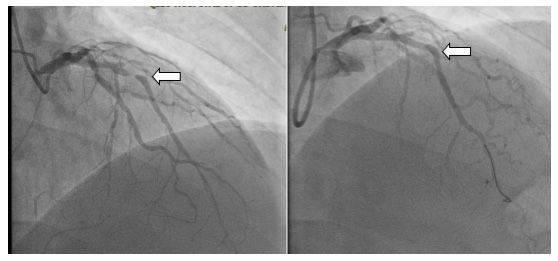

術前(左側圖)與生物可吸收支架術后(右側圖)血管血流對比圖

首先應用藥物球囊開通了完全閉塞的右冠狀動脈,隨后成功應用藥物球囊解除了回旋支的嚴重狹窄,最后在前降支嚴重狹窄處成功植入生物可降解支架1枚,手術過程順利。術后,患者三支主要的冠狀動脈均順利完成再灌注治療,血管狹窄完全解除,患者癥狀明顯緩解。